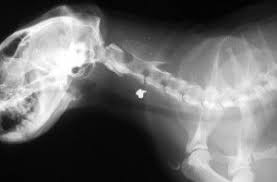

An X Ray Image Showing The Presence Of Kidney Stones In A Small Clawed Otter Smithsonian Stone Image Shows

Herbal treatment at dr. A pica case confused with renal and bladder stones source. These images can be fetched after conducting tests using abdominal x ray contrast radiography or ultrasound equipment.